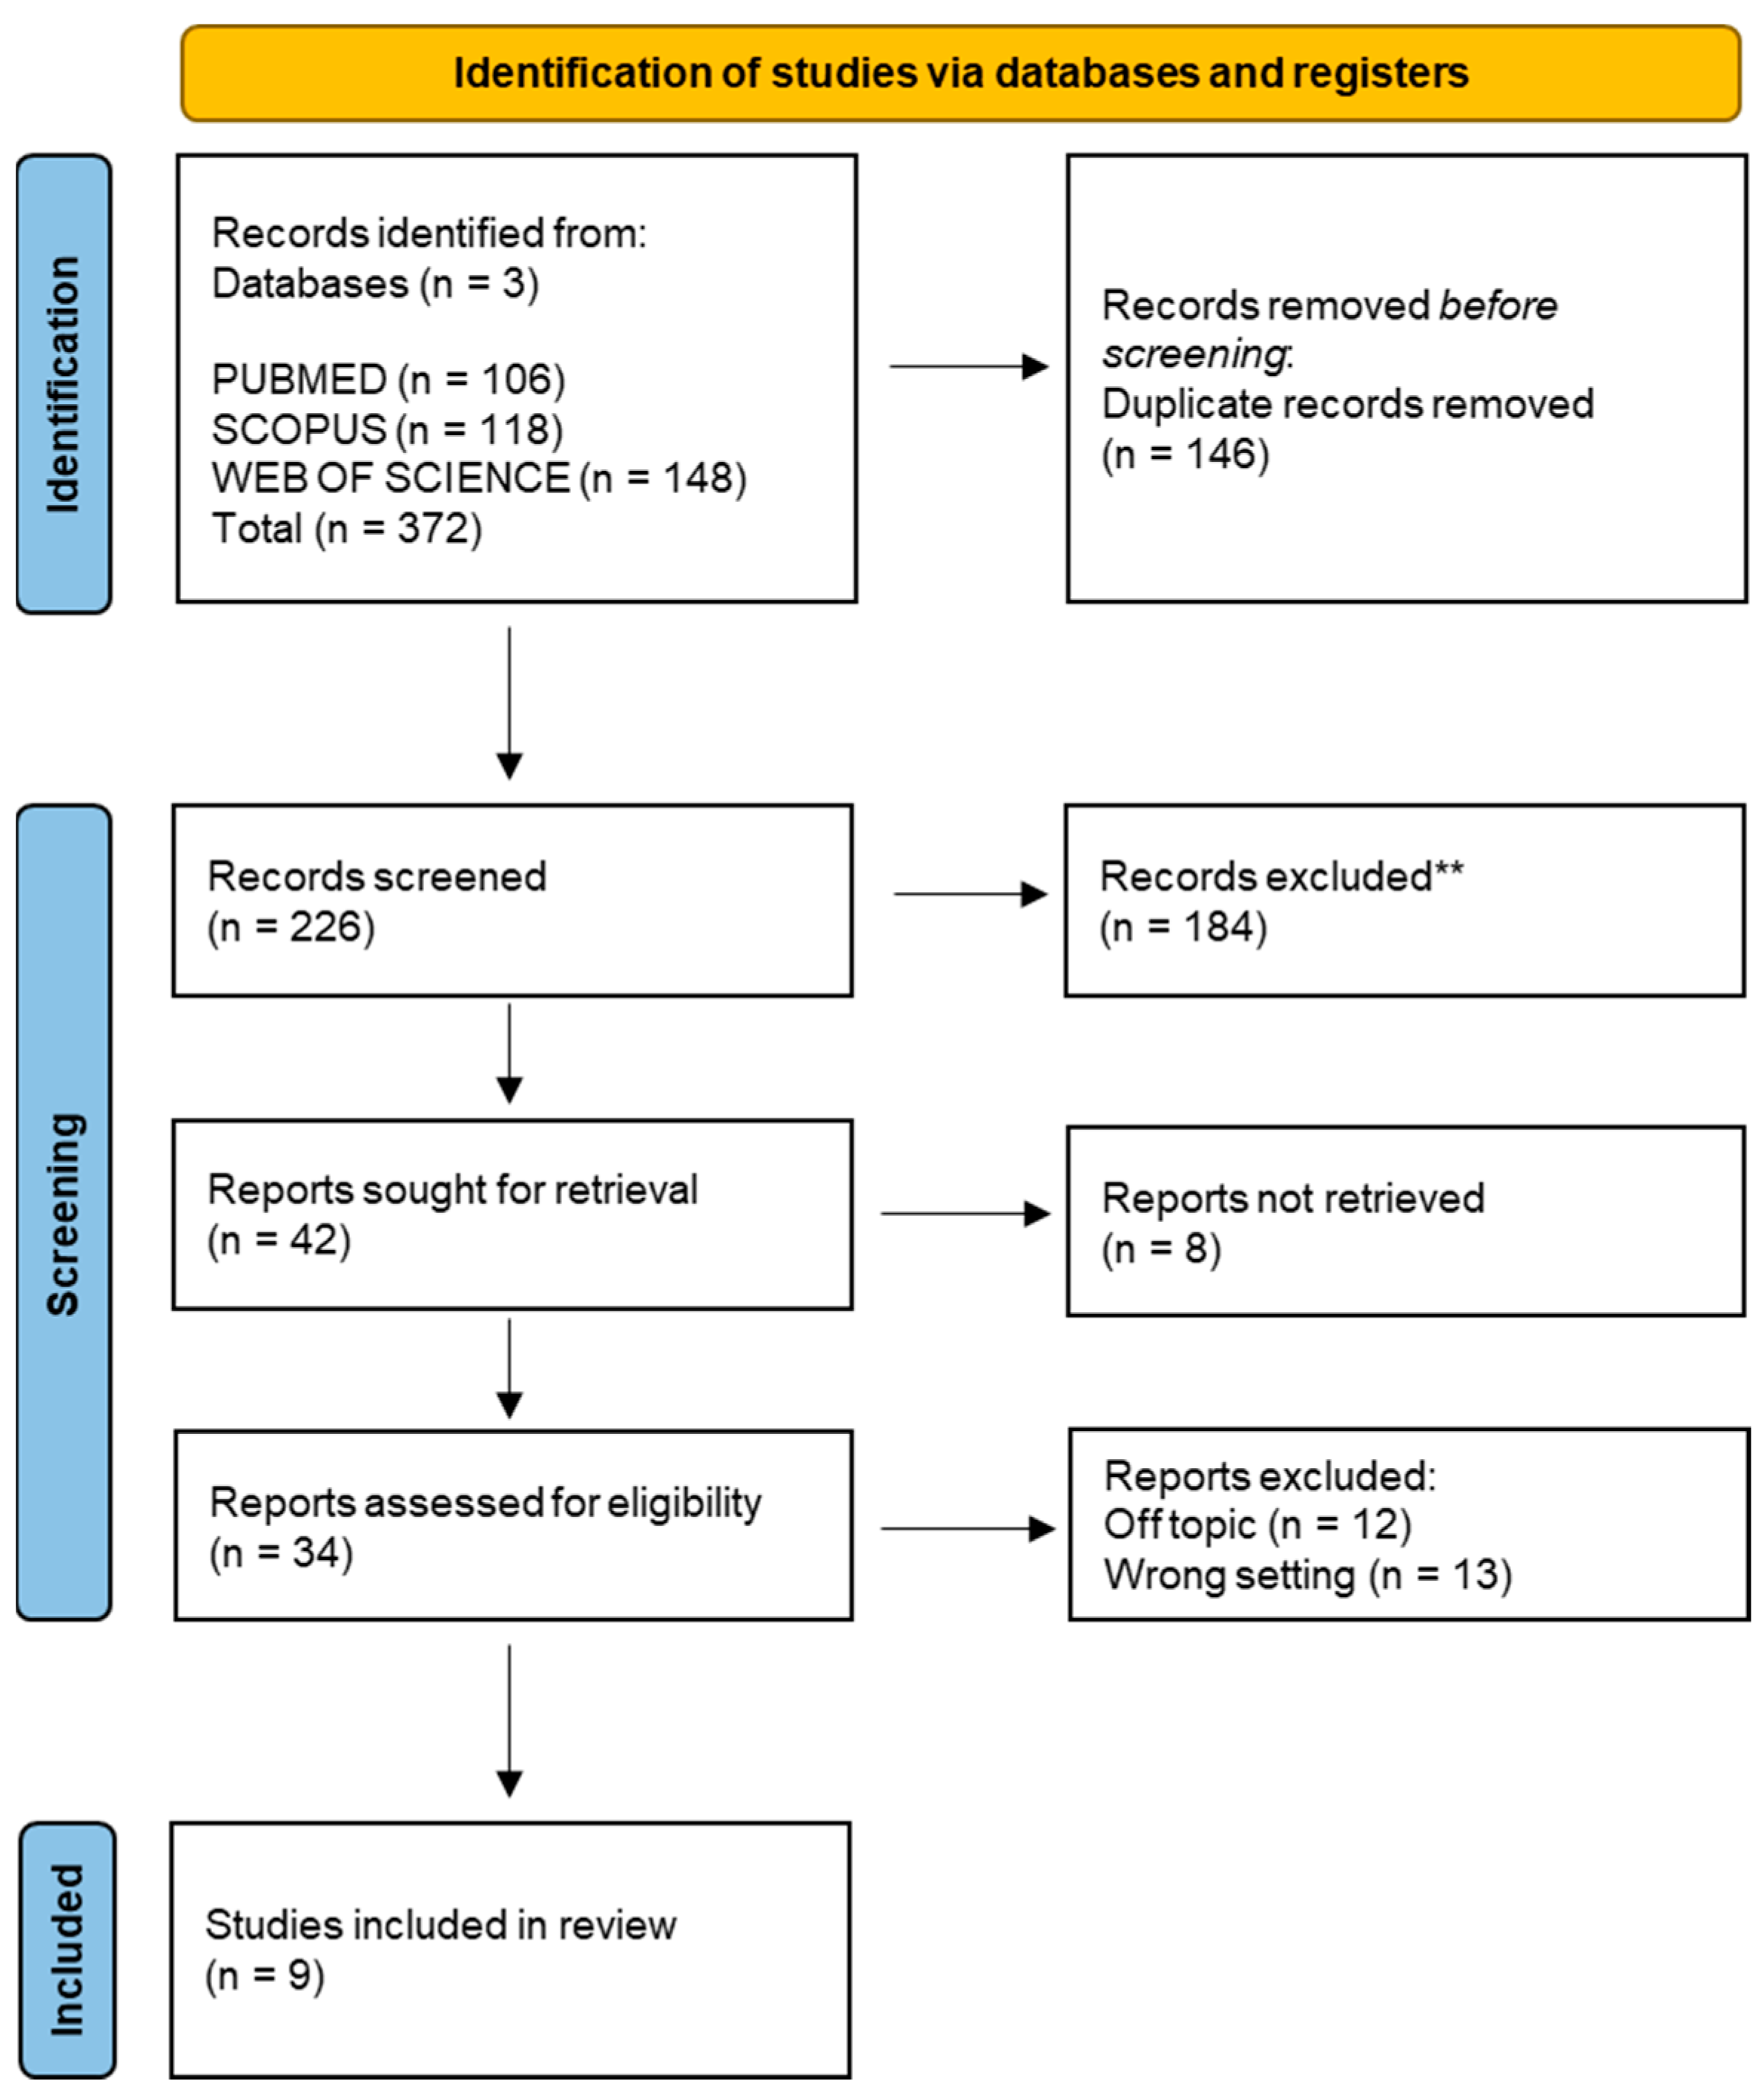

2. Materials and Methods

3. Results

General Characteristics of the Articles Included